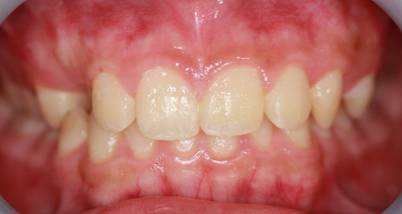

インビザGOによる矯正症例1 16歳男性

マウスピース矯正開始前。右上犬歯が内側にありました

前から見たところ